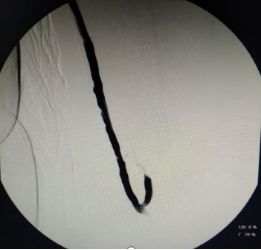

血液净化中心医生DSA下行血管造影+开通左、右无名静脉的手术过程

03. DSA下中心静脉再通术

孙某某 男 69岁,尿毒症,静脉压力高达260mmhg,左上臂静脉曲张像“蚯蚓”一样,左上臂及右颈部可见膨大静脉瘤形成,检查提示左无名静脉全段闭塞。

血管“下游”堵起了,血液就从脑壳皮小血管流向对侧颈部静脉血管再汇入心脏,导致病人血管“鼓包”、头痛,睡不好觉。要想解决这个问题,首选方案是开通血管,也就是说哪里的路堵了修通哪里的路。这个病人的血管堵得很长,堵塞部位迂曲位于胸腔并靠近心脏,导丝软头配合导管无法“捅过”堵塞部位。

经过讨论,为该患者采取了DSA下使用导丝硬头配合导管锐性开通左无名静脉方案,安岳县人民医院是四川省第一个开展这一技术的县级医院。锐性开通血管风险高,面临“捅穿”血管大出血、损伤心肺临近器官风险。血液净化中心医生精心操作,成功用导丝通过闭塞部位后再使用球囊扩张导管扩张左无名静脉。